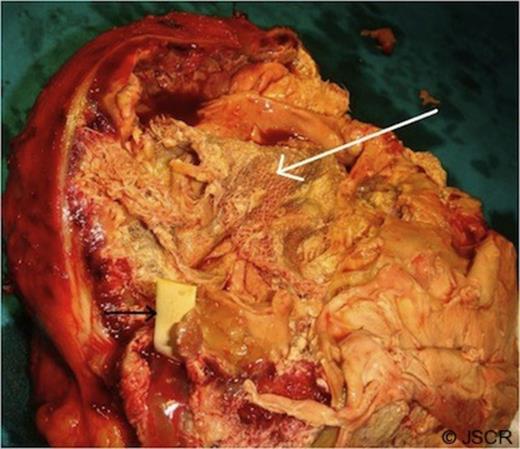

A radio-opaque material was seen in the lesion raising the suspicion of a foreign body. Common bile duct was dilated and contained a stone which was removed endoscopically. At exploration, a large globular lesion was found which was densely adhered to the adjacent structures (anterior abdominal wall, omentum, transverse colon, and antrum of the stomach). En-bloc resection of the mass along with the adhered transverse colon was done (Figure-2). Cut section of the mass showed a large surgical sponge and a foreign body within it (Figure-3).The patient had an uneventful recovery and she was well at 19-month follow-up.

Cut section of the mass showing a large sponge (white arrow) and a radio-opaque marker (black arrow) within it.